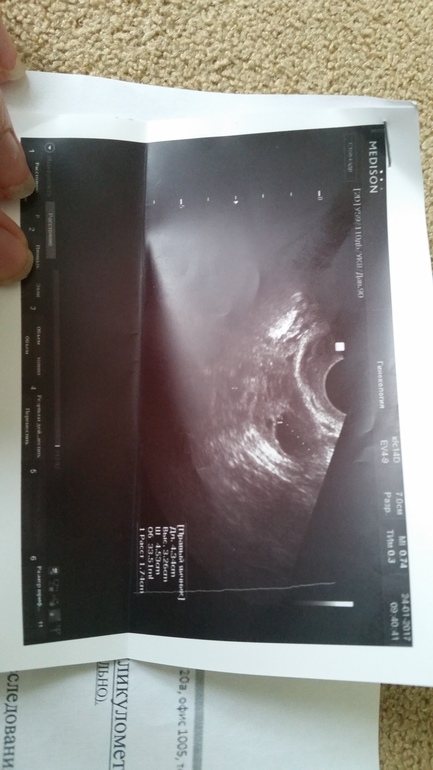

Что мы имеем:

Вуаля! Поликистоз.

Дала направление на анализы и повторное узи, чтобы потвердить или опровернуть спкя. Ну и мужу сдать СГ. Но я больше чем уверена что потвердится.